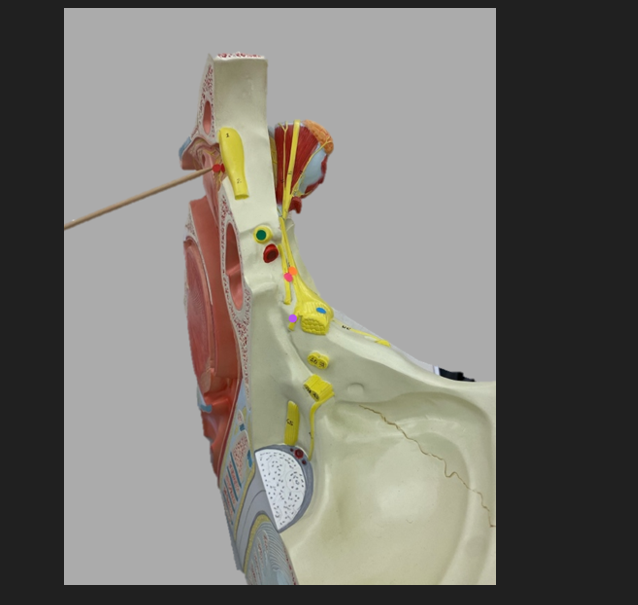

green dot

spinal nerve

orange dot

ventral root

pink dot

dorsal root

blue dot

dorsal root ganglion

red dot

dorsal ramus

yellow dot

ventral ramus

purple dot

anterior median fissure

red dot

posterior (dorsal) horn

purple dot

lateral horn

dark blue dot

anterior (ventral) horn

orange dot

dorsal column

yellow dot

lateral column

dark green

anterior column

line green and pink doit

gray commissure

light blue dot

posterior median sulcus